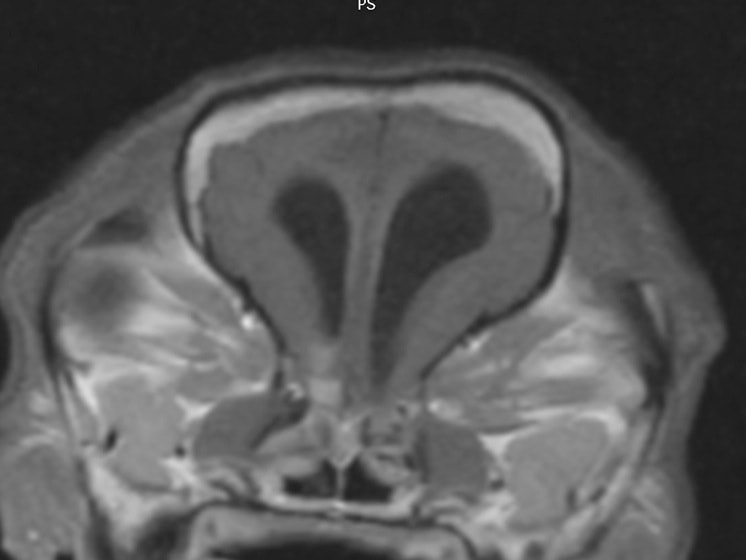

症例:フレンチブルドッグ 9歳 避妊雌

頭を撫でられるのを嫌がるという主訴で来院。来院時に頚部の圧痛を認めた。症状は消炎剤の投与により一時的に改善するが投与を終了すると直ちに再発するため、精査のためにMRI撮影を行った。

MRIの結果、頚部に脊髄空洞症を認め、頭部では水頭症および側脳室など脳内に数か所の腫瘤性病変を認めた。

頭蓋内伝播をしていることから悪性度の高い腫瘤である可能性が疑わしく、症例の頚部痛の原因と考えられる脊髄空洞症、および水頭症はこの頭蓋内腫瘤に起因する二次性発症と考えられる。

本症例の腫瘤は頭蓋内に数か所存在しており外科的切除や放射線療法は適応しにくいため、抗がん剤による化学療法の適応となった。

本症例は現在も抗がん剤(ロムスチン)による治療および脳圧降下剤などの投与であるが、症状も無く経過良好である。